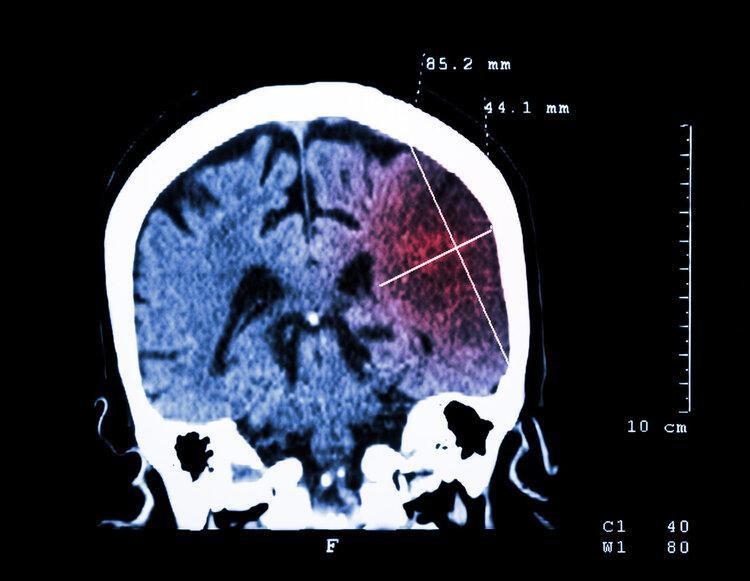

可沒成想這次洗澡馬先生在浴室摔倒,直接不省人事了,家人急忙撥打了急救電話,等到了醫院馬先生已經因腦出血而離世了

這樣的結果讓馬先生家人難以接受,明明身體很健康的他,怎麼會在洗澡時突然出現腦出血?